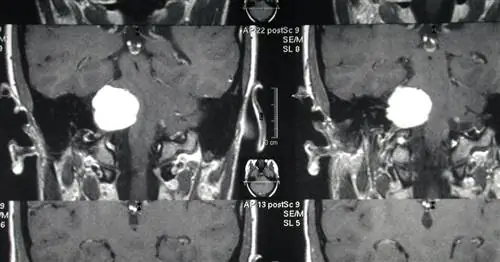

Опухоль головного мозга.

Он умер от злокачественной, безжалостной опухоли головного мозга, когда нашему сыну был год.